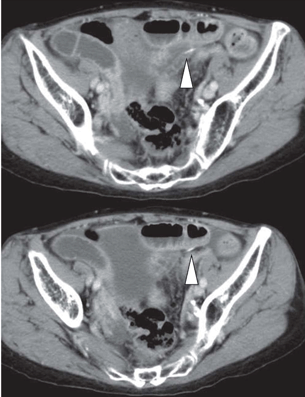

A 73-year-old female was presented to emergency department with a one-day history of increasing lower abdominal pain. The patient had attended a wedding party of her grandson and ate baked red snapper. Her past medical history was unremarkable and she was taking medication for hypertension. Her vital signs included blood pressure 119/66 mmHg, pulse rate 80 beats/min, and body temperature 36.2°C. On examination, the patient had a slightly distended abdomen with significant right iliac fossa guarding and tenderness. Her white cell count and C-reactive protein levels were 11900/mm3 and 1.24 mg/dL, respectively, indicating systemic inflammation. Abdominal computed tomography demonstrated pneumoperitoneum and fluid within the abdominal cavity, as well as dilated intestine, suggesting diffuse peritonitis due to alimentary tract perforation (Figure 1) (Figure 2). Under general anesthesia, the patient underwent diagnostic/therapeutic laparoscopy, which showed acutely inflamed ileum and purulent ascites. A foreign body, assumed to be a fish bone, was observed piercing through the small bowel wall at the ileum. As the site of perforation was not clearly determined via laparoscope, a lower median laparotomy was performed. Lavage of the abdominal cavity enabled us to detect a 2-mm ileal perforation by foreign body by confirming bubble from the perforation. Diffuse purulent peritonitis was evident in an area with adhesions. The foreign body was removed, primary suture of the intestinal perforation was performed, and the abdominal cavity was drained. Intravenous antibiotics were administered. The patient was discharged on day-5 after admission without complications.

Figure 2: Unenhanced abdominal computed tomography scan showing a fish bone (white arrowhead) as a linear radiopaque density penetrating the intestinal wall with adjacent areas of inflammation.

Diagnosis of foreign body perforation of the gastrointestinal tract can be challenging and is rarely correctly diagnosed preoperatively. Radiography is unreliable in the diagnosis of fish bone perforation. Computed tomography (CT) scan has been helpful in the detection of nonmetallic foreign body perforation. Fish bone perforation typically appears as a linear calcified lesion surrounded by an inflamed area on CT scan [6]. Evidence of pneumoperitoneum is only seen in approximately 30% of patients with intestinal perforation caused by fish bone ingestion [1]. Computed tomography scan sensitivity for detection of fish bone peritonitis is known to be relatively high (71–100%). Since the main reason for missed diagnosis is the observer’s lack of awareness, a high degree of clinical suspicion should be maintained in order to make a correct diagnosis.